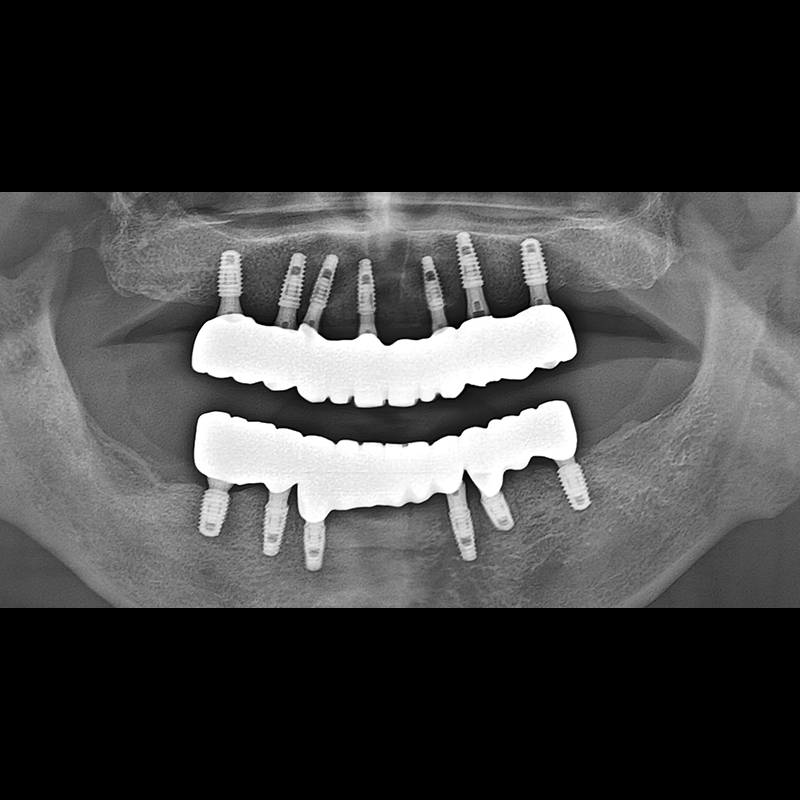

임플란트 전후사진 2025.05.30

결손된 치아 부분과 살리기 힘든 치아 위치에 임플란트를 식립하였습니다.